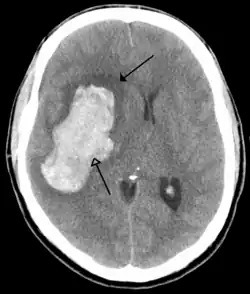

Tumours

Brain tumours can be either benign or cancerous. Most malignant tumours arise from another part of the body, most commonly from the lung, breast and skin.[178] Cancers of brain tissue can also occur, and originate from any tissue in and around the brain. Meningioma, cancer of the meninges around the brain, is more common than cancers of brain tissue.[178] Cancers within the brain may cause symptoms related to their size or position, with symptoms including headache and nausea, or the gradual development of focal symptoms such as gradual difficulty seeing, swallowing, talking, or as a change of mood.[178] Cancers are in general investigated through the use of CT scans and MRI scans. A variety of other tests including blood tests and lumbar puncture may be used to investigate for the cause of the cancer and evaluate the type and stage of the cancer.[178] The corticosteroid dexamethasone is often given to decrease the swelling of brain tissue around a tumour. Surgery may be considered, however given the complex nature of many tumours or based on tumour stage or type, radiotherapy or chemotherapy may be considered more suitable.[178]

Some treatments for stroke are time-critical. These include clot dissolution or surgical removal of a clot for ischaemic strokes, and decompression for haemorrhagic strokes.[196][197] As stroke is time critical,[198] hospitals and even pre-hospital care of stroke involves expedited investigations – usually a CT scan to investigate for a haemorrhagic stroke and a CT or MR angiogram to evaluate arteries that supply the brain.[195] MRI scans, not as widely available, may be able to demonstrate the affected area of the brain more accurately, particularly with ischaemic stroke.[195]